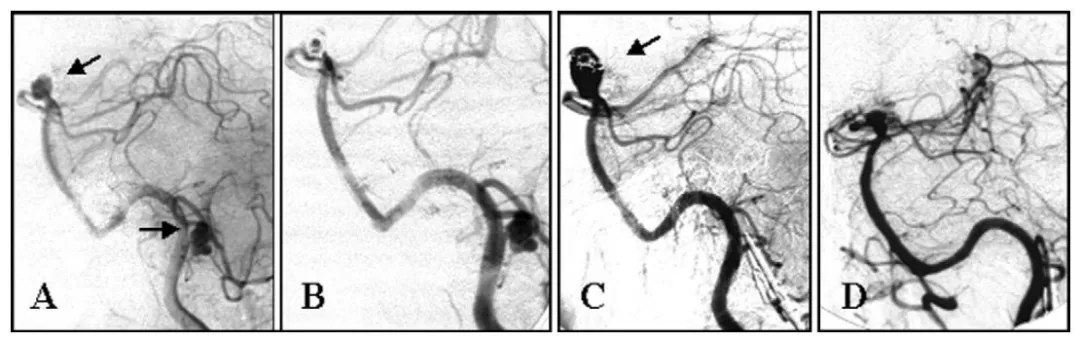

另一位62岁女性,基底动脉顶端动脉瘤在栓塞两年后复发,再次栓塞尝试失败,最终通过显微手术成功夹闭,术后3个月恢复正常日常生活。

(A)左侧椎动脉造影显示基底动脉顶端动脉瘤及左侧小脑后下动脉动脉瘤(箭头所示)。

(B)基底动脉动脉瘤经弹簧圈次全栓塞,小脑后下动脉动脉瘤初期未处理。

(C)弹簧圈栓塞术后2年随访造影显示基底动脉顶端动脉瘤复发(箭头所示),小脑后下动脉动脉瘤已闭塞。

(D)基底动脉动脉瘤夹闭术后1年随访造影。